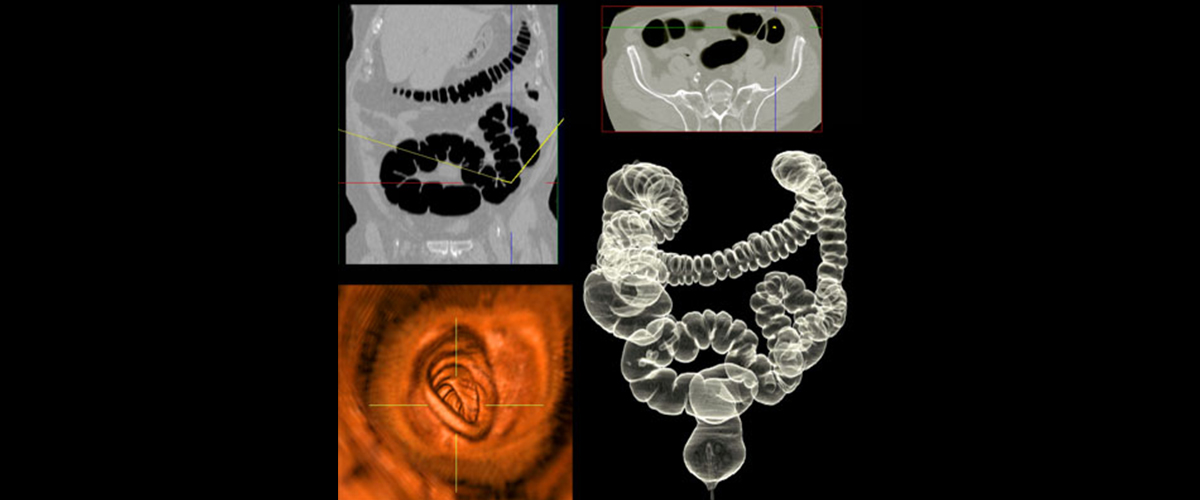

CT VIRTUAL COLONOSCOPY

DRCTC is proud to have a mobile CT scanner. This system boasts a wide variety of revolutionary advancements, including being the only Open Gantry Design CT in the marketplace. The system produces the fastest total body imaging time of any CT currently available and the multi-slice CT, allows for highly accurate and precise anatomical mapping.

scheduling

CT Virtual Colonoscopy are performed in both locations and must be scheduled.